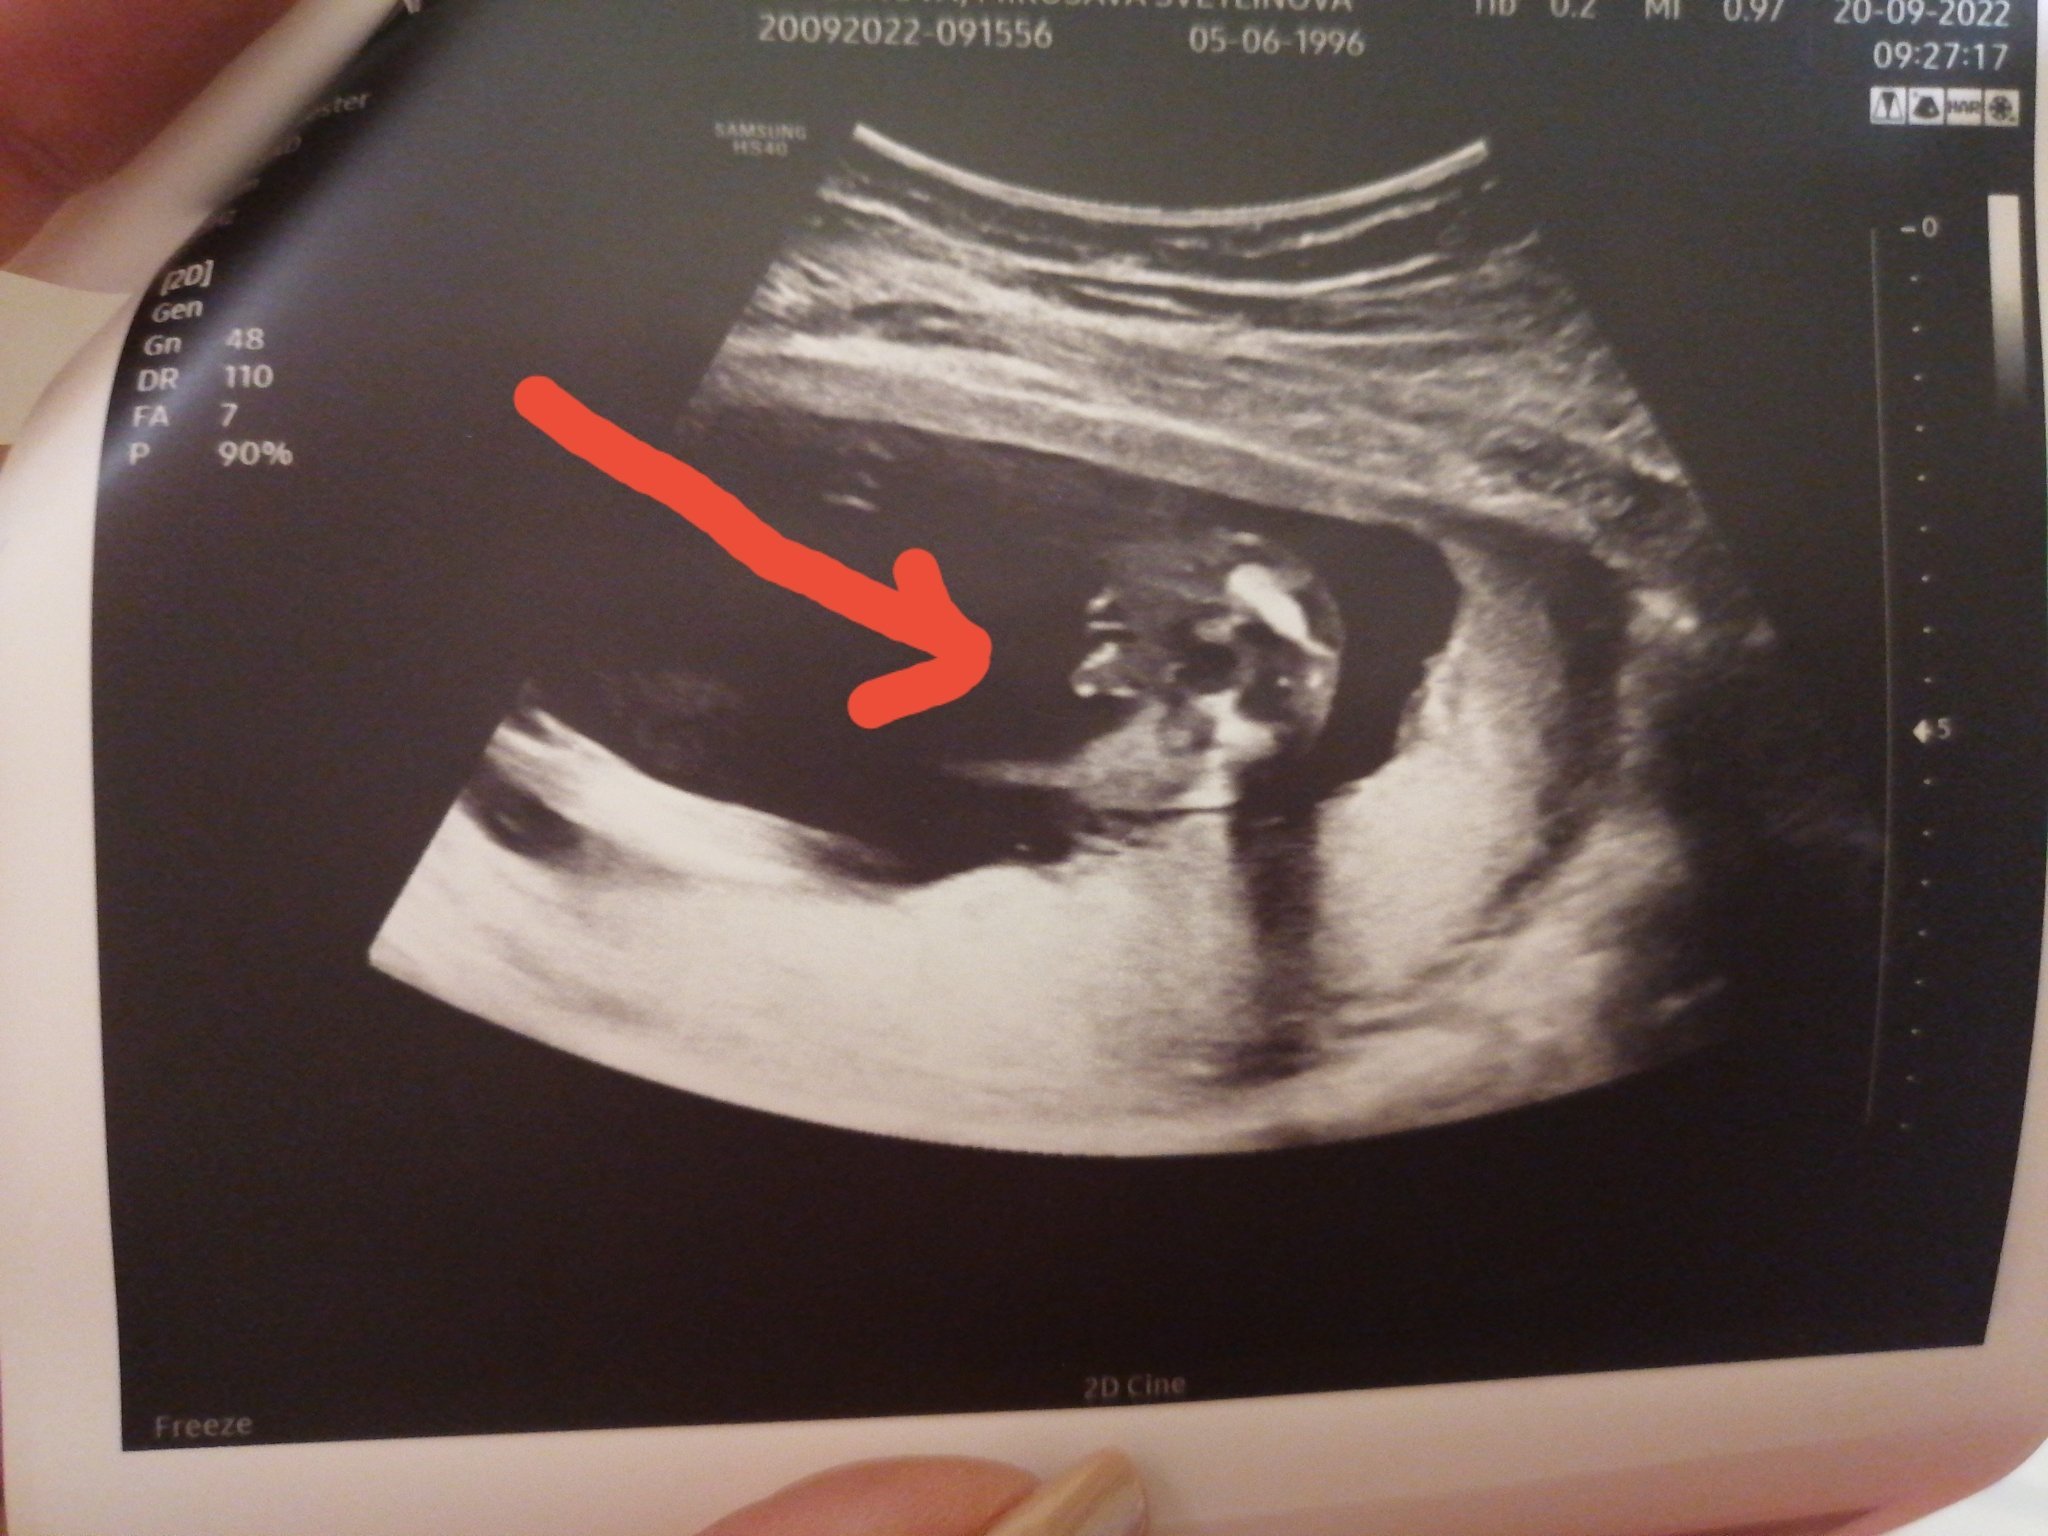

Какво представлява феталната морфология и защо е важна?